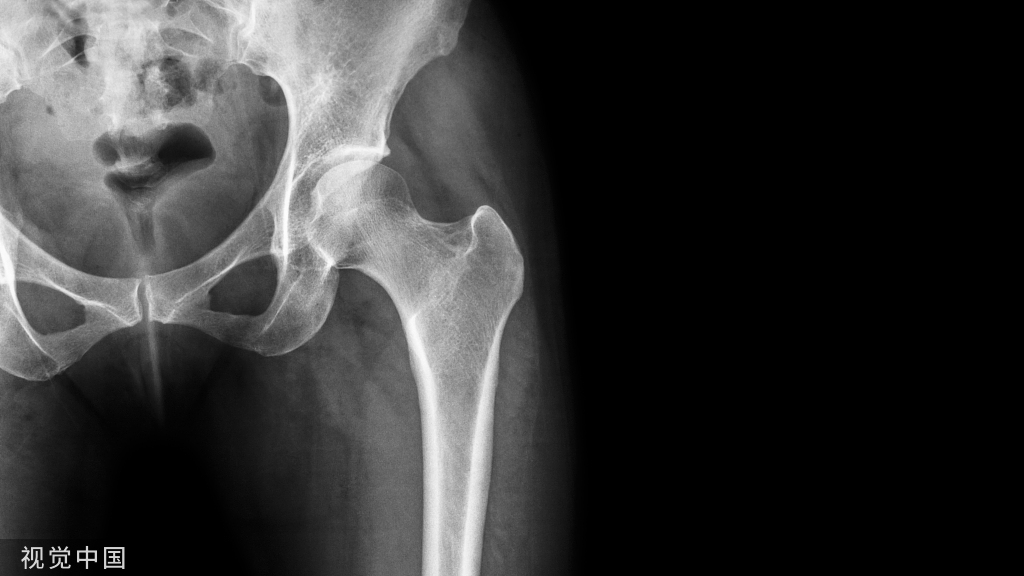

”骨水泥手术“ 病例展示

01

腰椎骨质疏松性骨折PVP